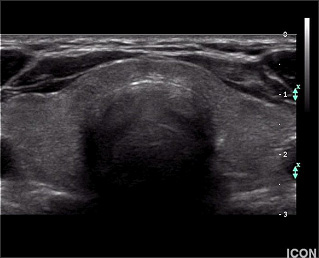

Το υπερηχογράφημα θυρεοειδούς είναι μία εξέταση για τη λήψη εικόνων του αδένα χρησιμοποιώντας κύματα υπερήχων (ηχητικά κύματα υψηλής συχνότητας). Τα κύματα αυτά διαπερνούν το δέρμα, αντανακλώνται στις εσωτερικές δομές του τραχήλου και μετατρέπονται σε σειρά εικόνων πραγματικού χρόνου μέσω του ηλεκτρονικού υπολογιστή. Το υπερηχογράφημα δεν εκπέμπει ακτινοβολία στον ασθενή, είναι απόλυτα ασφαλές για τον εξεταζόμενο και μπορεί να επαναλαμβάνεται συχνά. Μπορεί να αποκαλύψει όζους ακόμα και 2-3 χιλιοστών. Η υπερηχογραφία μπορεί καταρχήν να διαχωρίσει τους κυστικούς όζους του θυρεοειδούς (όζοι που περιέχουν υγρό) από τους συμπαγείς. Οι κυστικοί όζοι είναι συνήθως καλοήθεις, ενώ οι συμπαγείς είναι δυνητικώς κακοήθεις. Οι περισσότεροι όζοι, ωστόσο, έχουν και κυστικά και συμπαγή στοιχεία, ενώ οι αμιγώς κυστικοί είναι σχετικά σπάνιοι. Συνεπώς, η υπερηχογραφία από μόνη της σπανίως μπορεί να πιστοποιήσει το διαχωρισμό μεταξύκαλοήθους και κακοήθους όζου. Μία πολύτιμη βοήθεια των υπερήχων είναι στο να καθοδηγήσουν τη βελόνα βιοψίας σωστά, ούτως ώστε να ληφθεί επαρκές δείγμα από την ύποπτη βλάβη για κυτταρολογική εξέταση. Η καθοδήγηση αυτή επιτρέπει τη λήψη δείγματος από το συμπαγές τμήμα των όζων που είναι και κυστικοί και συμπαγείς. Έτσι, αποφεύγεται η παρακέντηση του γειτονικού φυσιολογικού θυρεοειδικού ιστού σε μικρούς όζους.

Ακόμα και όταν η βιοψία θυρεοειδούς δείξει καλοήθεια, το μέγεθος του όζου θα πρέπει να παρακολουθείται. Το υπερηχογράφημα παρέχει αντικειμενικό και ακριβή τρόπο ανίχνευσης μεταβολών στο μέγεθος του όζου. Ένας καλοήθης όζος (από τη βιοψία) που παραμένει σταθερός σε μέγεθος ή που φαίνεται να μικραίνει σε διαδοχικά υπερηχογραφήματα, δεν είναι πιθανό να είναι κακοήθης και να απαιτεί χειρουργική αφαίρεση. (Εικόνα Β, Γ).

Εικόνα Β (Φυσιολογικός θυρεοειδής αδένας σε υπερηχογράφημα)